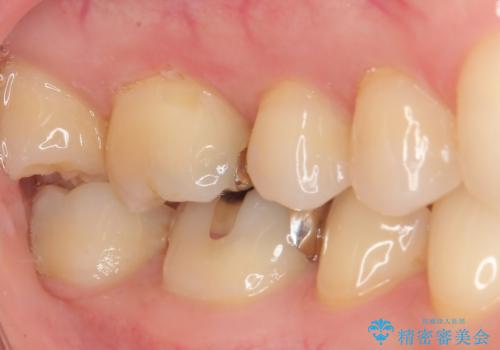

- 銀歯をやり替えたいとのことで来院された患者様です。金属の詰め物の大きさ、虫歯の範囲を考慮してオールセラミッククラウンでの治療をご提案しましたが、患者様のご希望であまり歯を削りたくないとのことでハイブリッドインレーでの治療を行うことにしました。

拡大鏡視野下で、金属の詰め物(メタルインレー)、虫歯の除去を行い、ハイブリッドインレーに適した形に整えました。